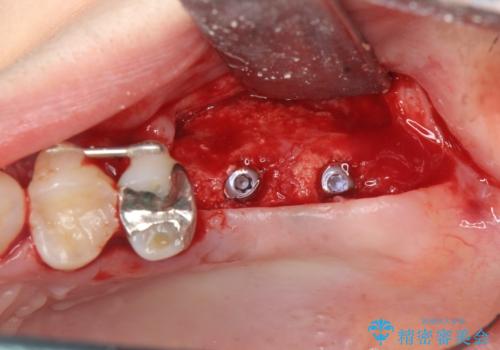

奥歯を2本失ったのち、しっかりと噛める環境へと整備するため、しっかりと骨の造成を行い清掃性を高めたインプラント治療を行っていくこととしました。

- 110万円(インプラント×2・チタンカスタムアバットメント×2・ジルコニアクラウン×2・仮歯×2・ 骨造成・サイナスリフト)費用は治療当時の料金となります

インプラントの仕上がりを見越して、ただ埋入するだけではなく長期的な予後を見込むには清掃のしやすい環境を整備することが大切です。

今回は大きく吸収してしまった歯槽骨をしっかりと造成することで、歯間ブラシを行いやすいインプラント周囲環境を整備することができました。